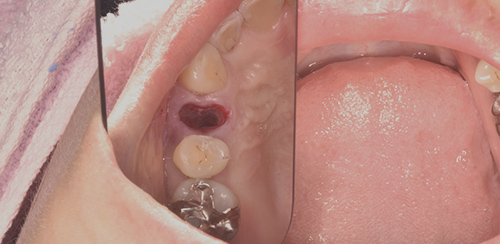

抜歯後

治療後